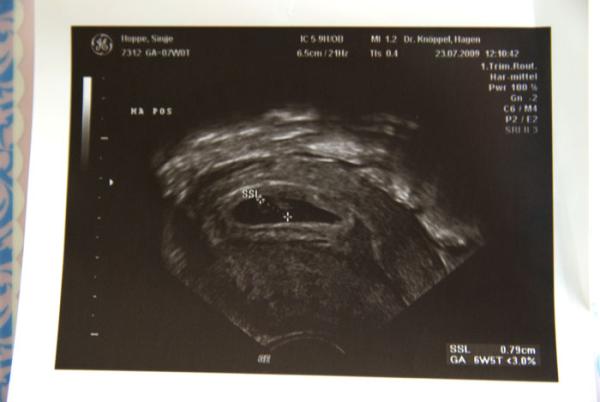

Hier ist das US Bild bei 5+4

Bild zu US bIlder - Forum für März - Mamis